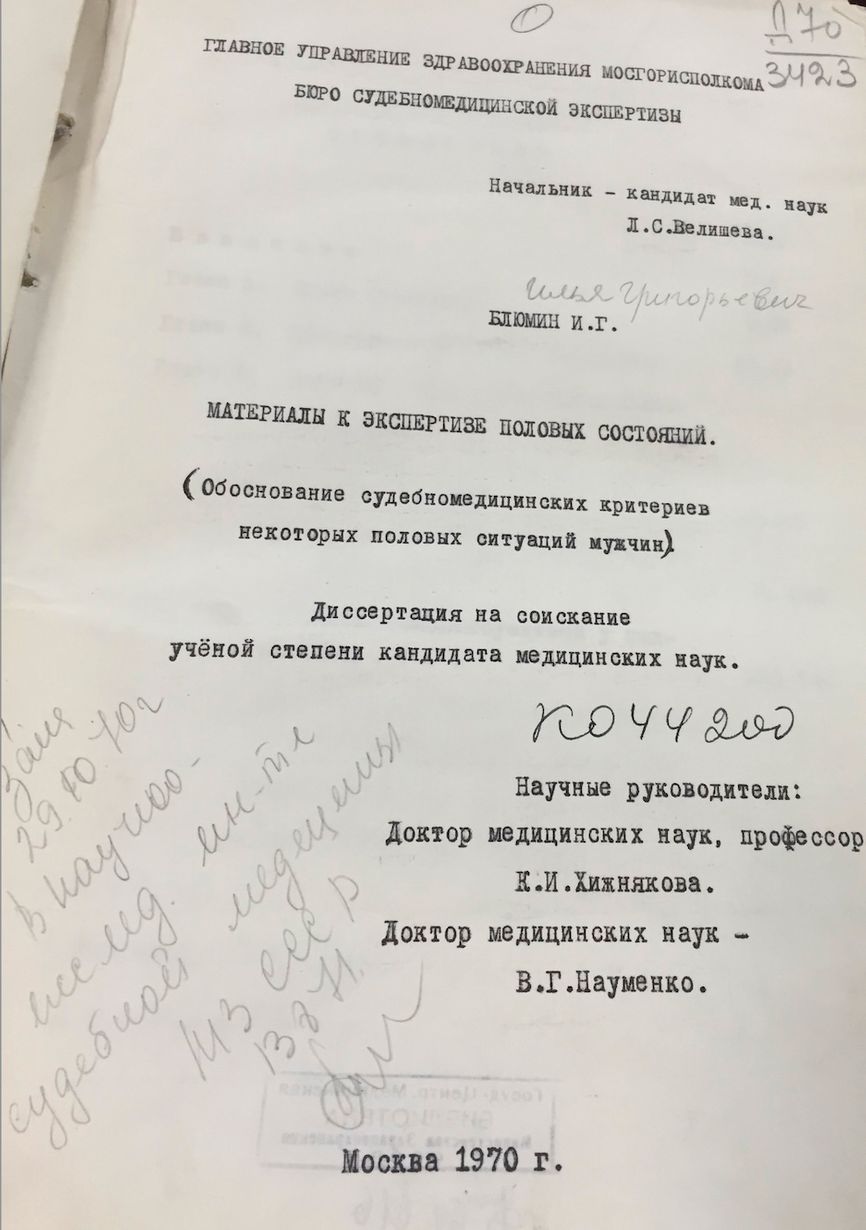

Особенно тесно медики и правоохранительные органы СССР сотрудничали в сфере борьбы с «мужеложеством». Так, в 1970 году сотрудник Московского бюро судебно-медицинской экспертизы Иван Блюмин написал целую диссертацию о том, как выявить признаки совершенного полового акта между двумя мужчинами по их половым органам. Милиция охотно поставляла ему «преступников», а Блюмин охотно их исследовал. Тем не менее снабдить МВД конкретными инструкциями по обнаружению признаков «мужеложества» Блюмину не удалось. Судмедэксперт ограничился лишь общими рекомендациями.